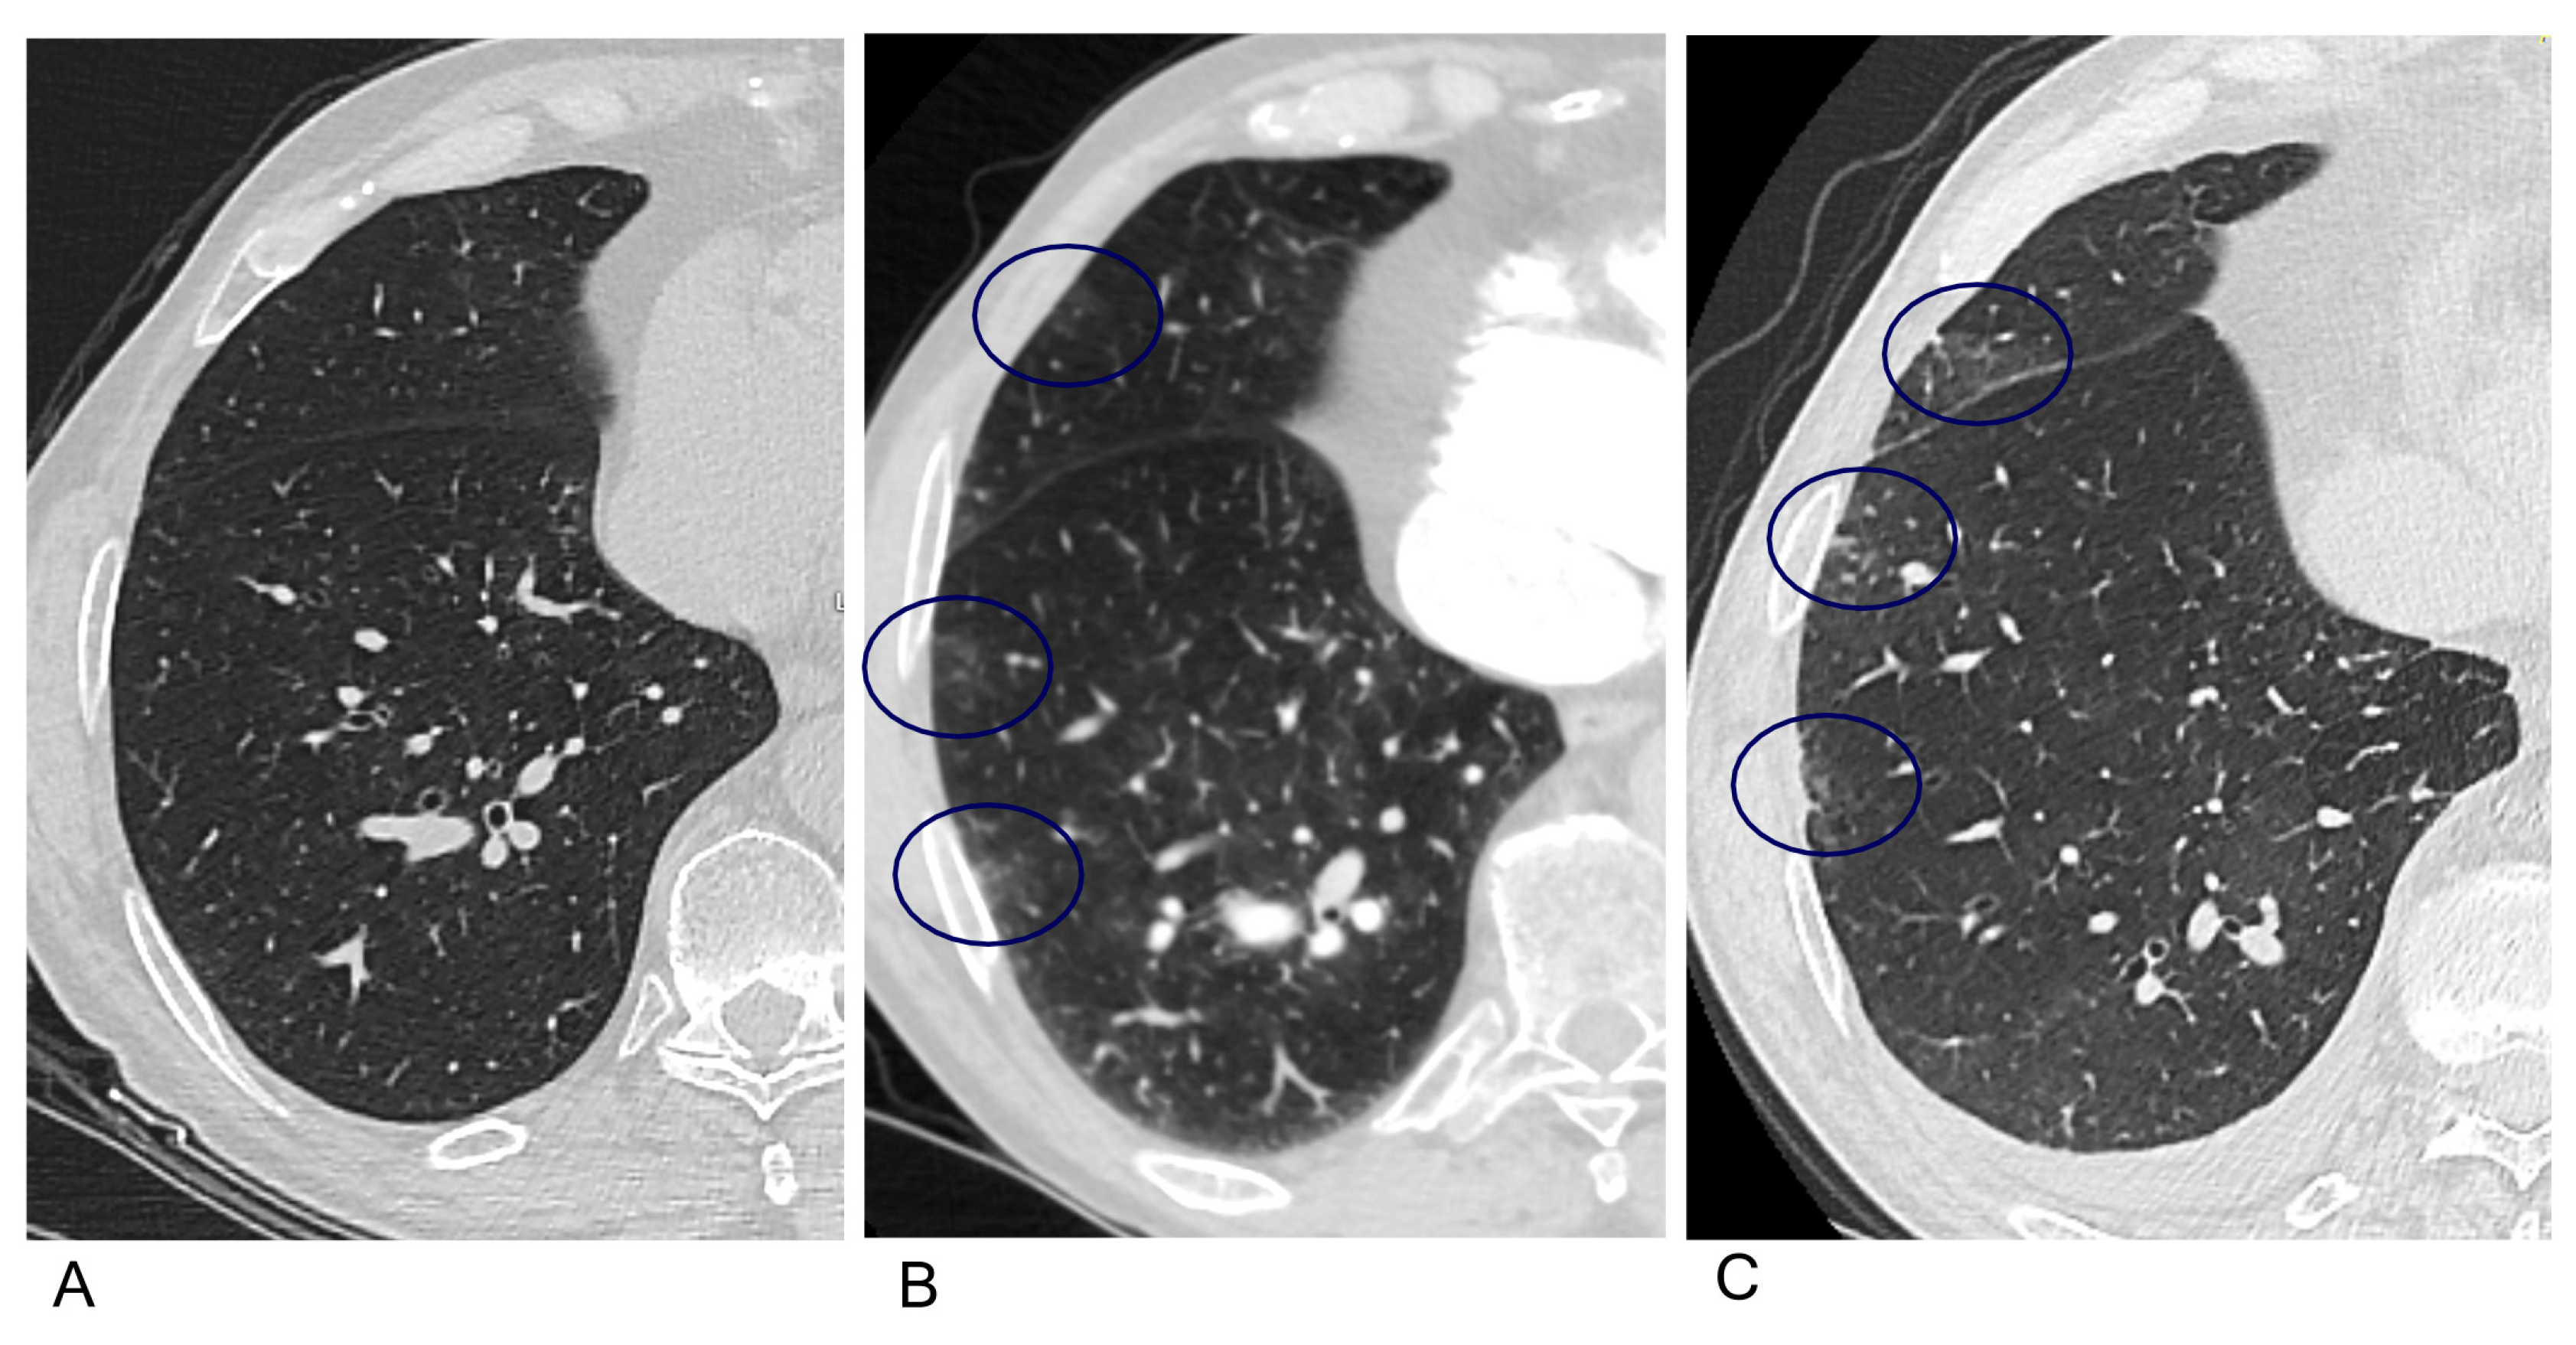

3.4. Computed Tomography Pulmonary Angiography (CTPA) Subgroup